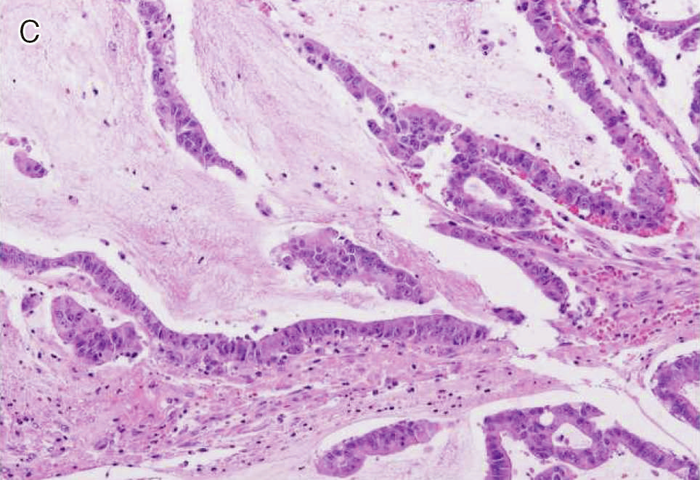

Ⅲ-2-1-2 ミスマッチ修復(MMR)異常を示す大腸癌に特徴的な病理組織学的所見

- MMR異常を示す大腸癌ではその他の大腸癌と比べ,いくつかの組織学的特徴が,より高頻度に認められる。改訂Bethesdaガイドライン28においては,①腫瘍内リンパ球浸潤

(tumor infiltrating lymphocytes:TIL),②髄様増殖,③粘液癌・印環細胞癌様分化,④Crohn様リンパ球反応(Crohn’s-like lymphocytic reaction)の4項目が挙げられている(図Ⅲ-3)。ただし,これらの病理組織学的特徴は必ずしもリンチ症候群に特有のものではなく,散発性MMR異常大腸癌にも共通して認められる58)。

図Ⅲ-3 MSI-High大腸癌の病理組織学的特徴

| A: | 腫瘍内リンパ球浸潤。腫瘍上皮内にhaloを伴ったリンパ球浸潤を認める。 |

| B: | 髄様増殖。腫瘍細胞は腺管を形成せず,充実性胞巣状の増殖を示す。 |

| C: | 粘液癌。多量の細胞外粘液を伴う。 |

| D: | Crohn様リンパ球反応。腫瘍周囲に多数のリンパ球の集簇巣を認める。 |